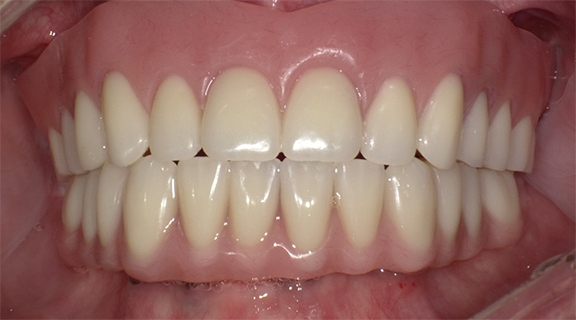

An implant-retained and implant-supported removable prosthesis may be fabricated by using a bar or a conical, titanium abutment with a 5-degree taper (Figure 18).49 In the next case, a fixture-level impression was made and records were registered and sent to the laboratory with the abutments (preselected based on the height of the mucosal cuff) for framework and prosthesis fabrication.49 The prosthesis had recesses on its intaglio surface to permit pickup of the abutment caps (Figure 19).49 The abutments were attached to the implants in the mouth (Figure 20). A jig/index provided by the laboratory (Figure 21) was used to seat the abutments intraorally so that they were positioned exactly as they were on the master cast. Gold caps were placed over the abutments and were picked up in the prosthesis intraorally (Figure 22).49 (Gold caps that fit over the abutments provide excellent retention, which improves over time.)50 The prosthesis was adjusted, finished, polished, and placed in the mouth (Figure 23). The prosthesis was entirely supported by the implant abutments.49 It had excellent retention and stability (almost like a fixed restoration) because it was entirely implant-supported; yet, it was removable.49

Fig 23. The prosthesis was placed in the patient’s mouth.

Figure 23